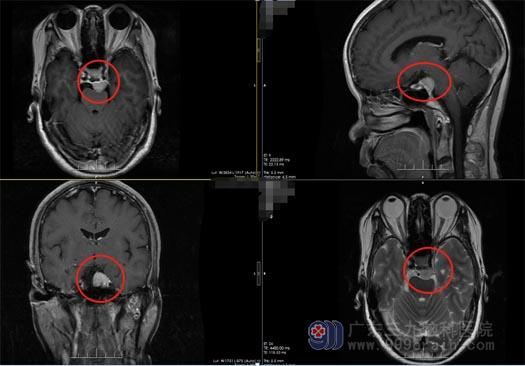

得知消息后,陈阿姨一家人焦急地四处打听,经朋友介绍,他们来到了广东三九脑科医院神经外五科。主管医生毕中胜给陈阿姨安排了头颅MRI和CTA检查,CTA结果显示:蝶鞍后方偏左侧占位性病变, MR结果考虑岩斜区脑膜瘤。

2022年1月10号,鲁明副院长带领外五科手术团队为陈阿姨施行了“全麻下行内镜经鼻上中斜坡脑膜瘤切除术+颅底重建术”。手术很成功,双侧鼻腔填塞膨胀海绵止血,病人出血约200ml,未输血。术后第一天,陈阿姨即神志清醒、四肢活动正常,复查头颅肿瘤全切,未见颅内出血;1月21日顺利出院。